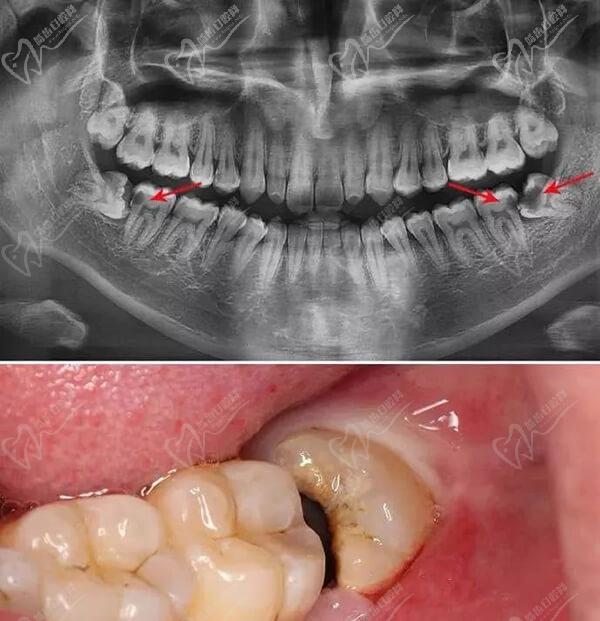

那么,面对下面的智齿建议您,赶快拔掉吧!

2、阻生智齿已经萌生不出希望的建议拔掉;

3、低于咬合平面的,不具备咬合功能建议拔掉;

4、完全埋伏在骨组织内,又称之为埋伏齿,建议拔掉;

5、智齿冠周炎的反复发作,引起面部的肿胀和疼痛建议拔掉;

6、导致食物嵌塞不容易清理,建议拔掉。